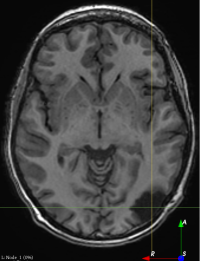

(f)

Figure 3: Manual labels from Rater A (green) and Rater D, the model trained with PubFull + EpiPre + Pseudo (magenta). Errors caused by a (a) small resection, (b) blood clot in cavity and (c) brain shift; segmentations corresponding to the (d) 50th, (e) 75th and (f) 100th percentiles giving a DSC of 81.7, 86.5 and 93.8, respectively.

We trained a model using PubFull, EpiPre and Pseudo (2371 images), obtaining a DSC of 81.7 (14.2). Adding the pseudo-labels to PubFull and EpiPre did not significantly improve performance (p=0.176𝑝0.176p=0.176), indicating our semi-supervised learning approach provided no advantage. Predictions from this model are shown in Fig. 3.

Predictions errors are mostly due to 1) resection of size comparable to sulci (Fig. 6a), 2) unanticipated intensities, such as those caused by the presence of blood clots in the cavity (Fig. 6b), 3) brain shift (Fig. 6c) and 4) white matter hypointensities (Fig. 6e). Further work will involve using different internal and external cavity textures, carefully sampling the resection volume, simulating brain shift using biomechanical models, and quantifying epistemic and aleatoric segmentation uncertainty to better assess model performance [24].